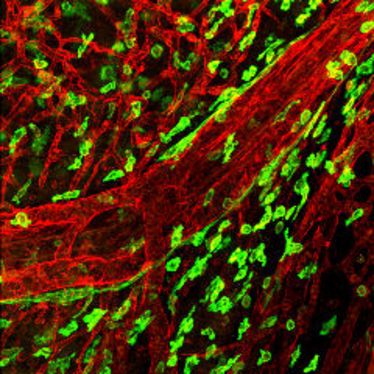

1. Small Animal Imaging Workshop in Münster

1. Small Animal Imaging Workshop in Münster

22.11.2010

- 26.11.2010

1. Small Animal Imaging Workshop in Münster

1. Small Animal Imaging Workshop in Münster

22.11.2010

- 26.11.2010

1. Small Animal Imaging Workshop in Münster

1. Small Animal Imaging Workshop in Münster